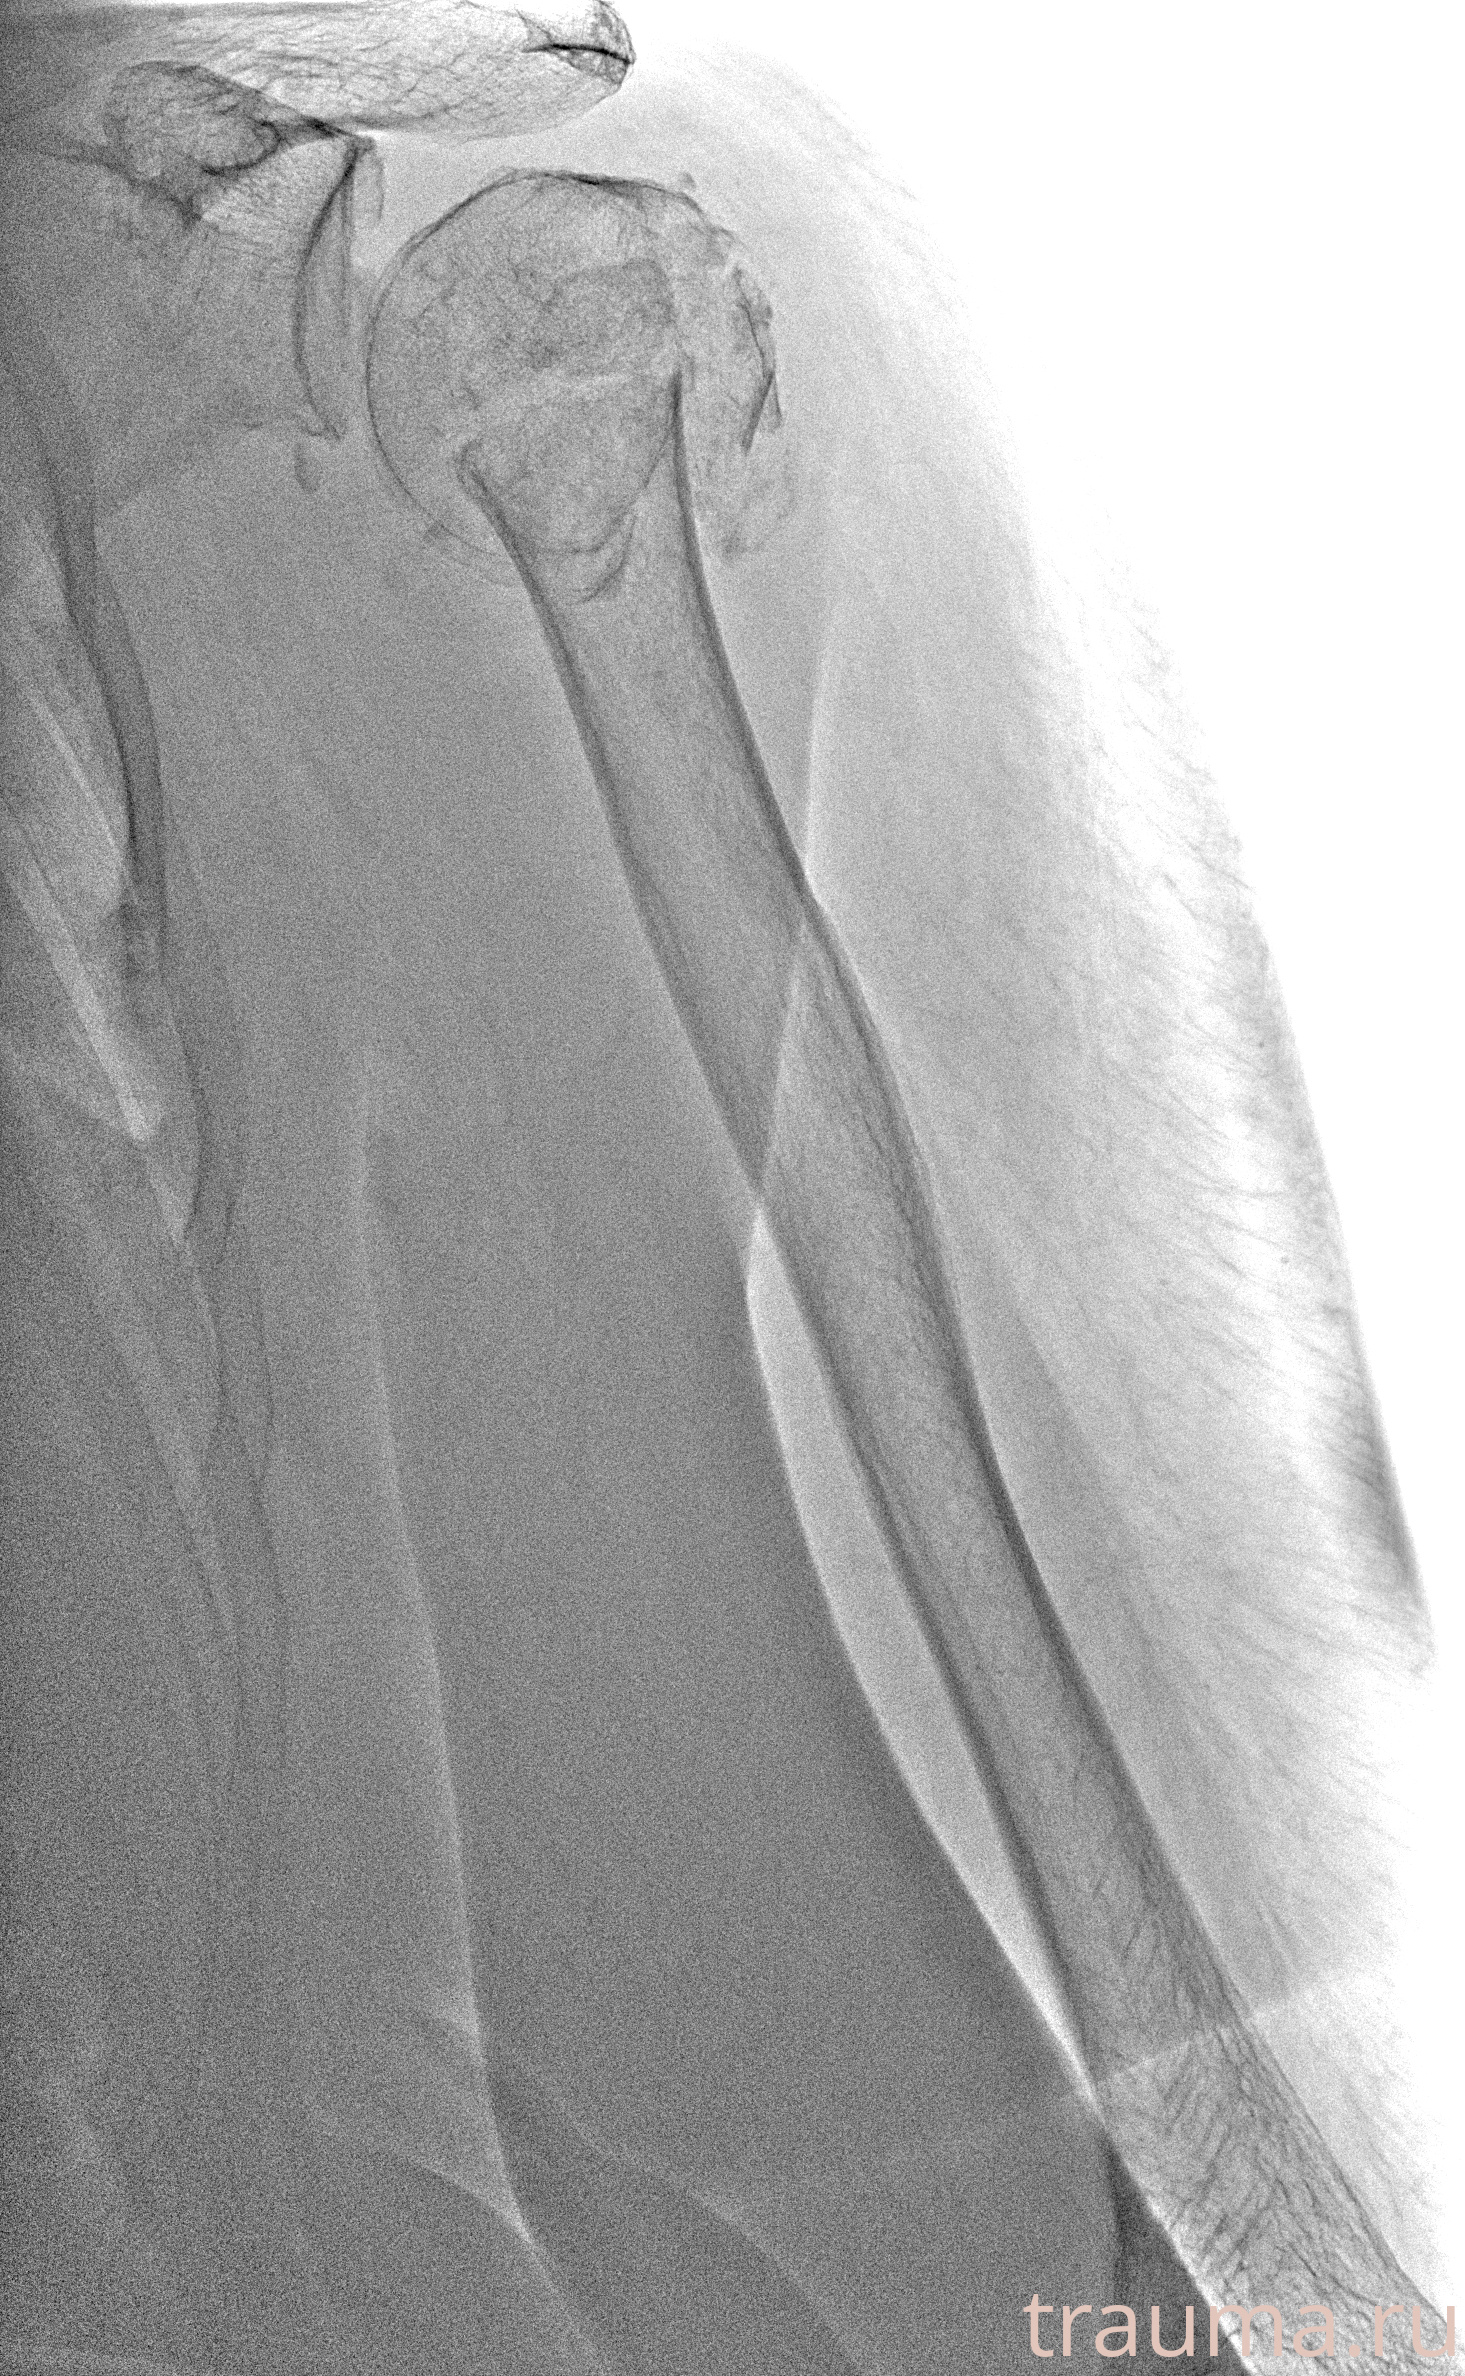

Рентгенограммы

Рентген на дому: по вашему адресу приезжает врач-рентгенолог, травматолог-ортопед с мобильным рентгеновским аппаратом, проводит диагностику травмы или заболевания, делает необходимые рентгенограммы, дает рекомендации по дальнейшему лечению. Получить качественные снимки в домашних условиях возможно благодаря уникальной методике, разработанной МосРентген Центром для института  Склифосовского